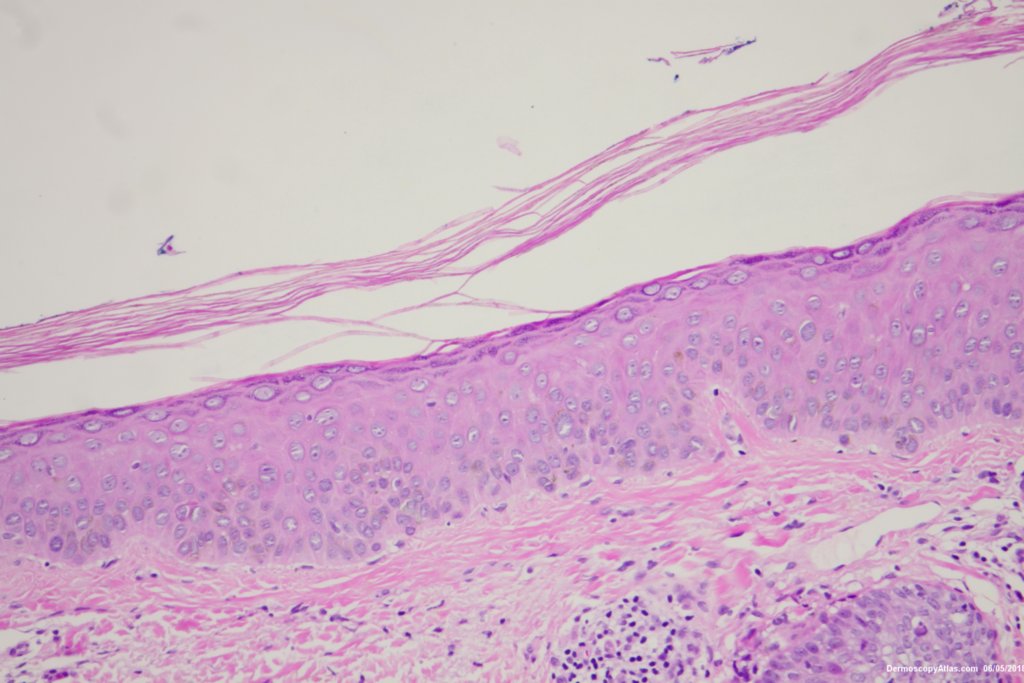

Diagnosis: Pigmented Intraepidermal carcinoma

Some pigmented lesions look melanocytic, However this is a pigmented intraepidermal carcinoma. Some areas show more full thickness atypia than others. The dermatoscopy shows some dots in rows but there are other grey dots showing regression at one edge.